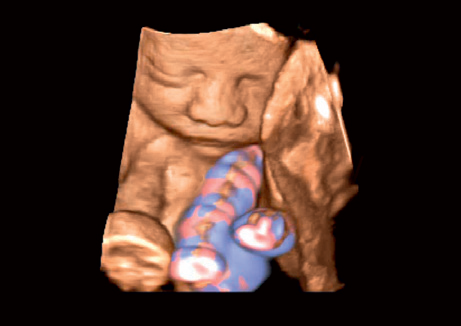

• STIC - исследование сердца плода в режиме объёмной визуализации

• 3D Color - цветное 3-х мерное изображение

• STIC Color - цветная объёмная визуализация сердца плода

• Трехмерная эхография в реальном времени с использованием специализированных 4D датчиков;

• Программа анализа сердца плода в трех проекциях в реальном времени 4D Stick;